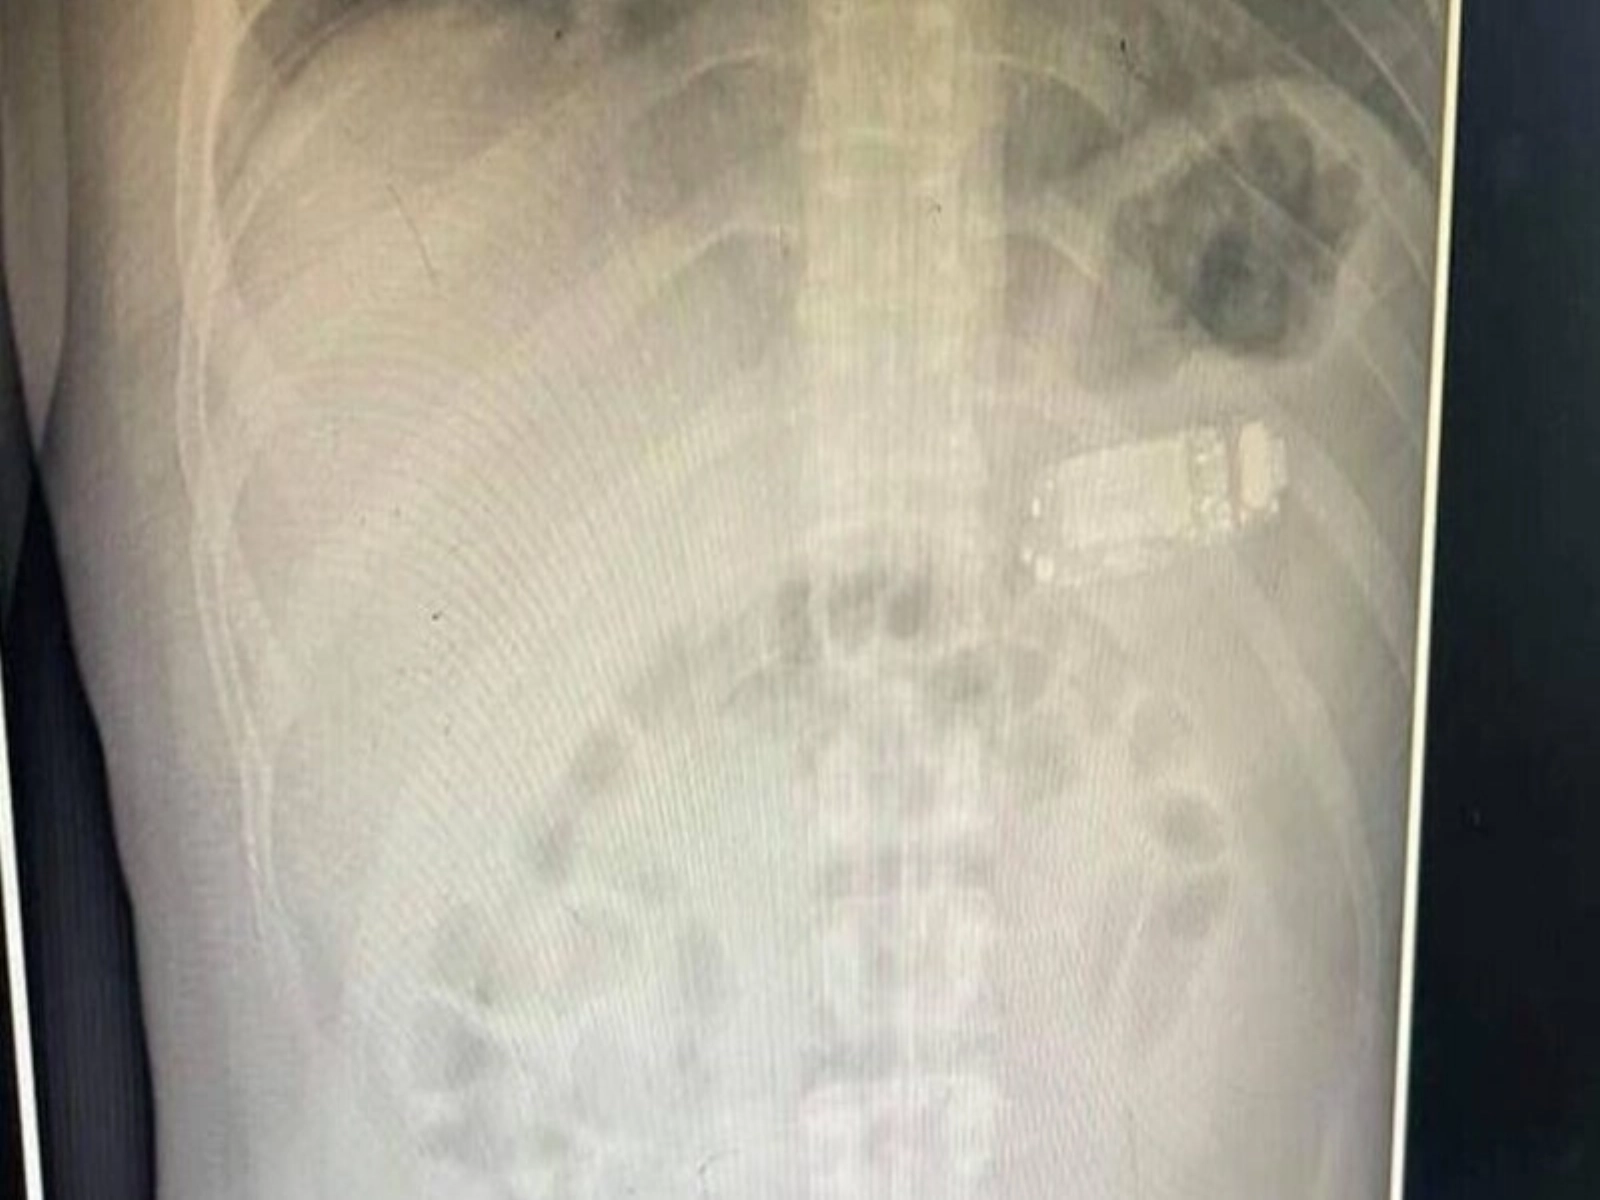

Medicul a constat că acesta avea un telefon marca Nokia în stomac.

”Deţinutul, în vârstă de 33 de ani, a înghiţit un telefon mic, pe care am reuşit să-l scoatem”, a declarat telefonic AFP gastroenterologul, care a condus echipa care a efectuat intervenţia, Skender Telaku.

”Cu mijloace endoscopice, fără să deschidem stomacul, am scos telefonul rupt în trei”, a precizat el.

Poliţia l-a preluat apoi pe pacient, dar şi telefonul Nokia 3310, un model comercializat iniţial de marca finlandeză în anii 2000, a precizat gastroenterologul.